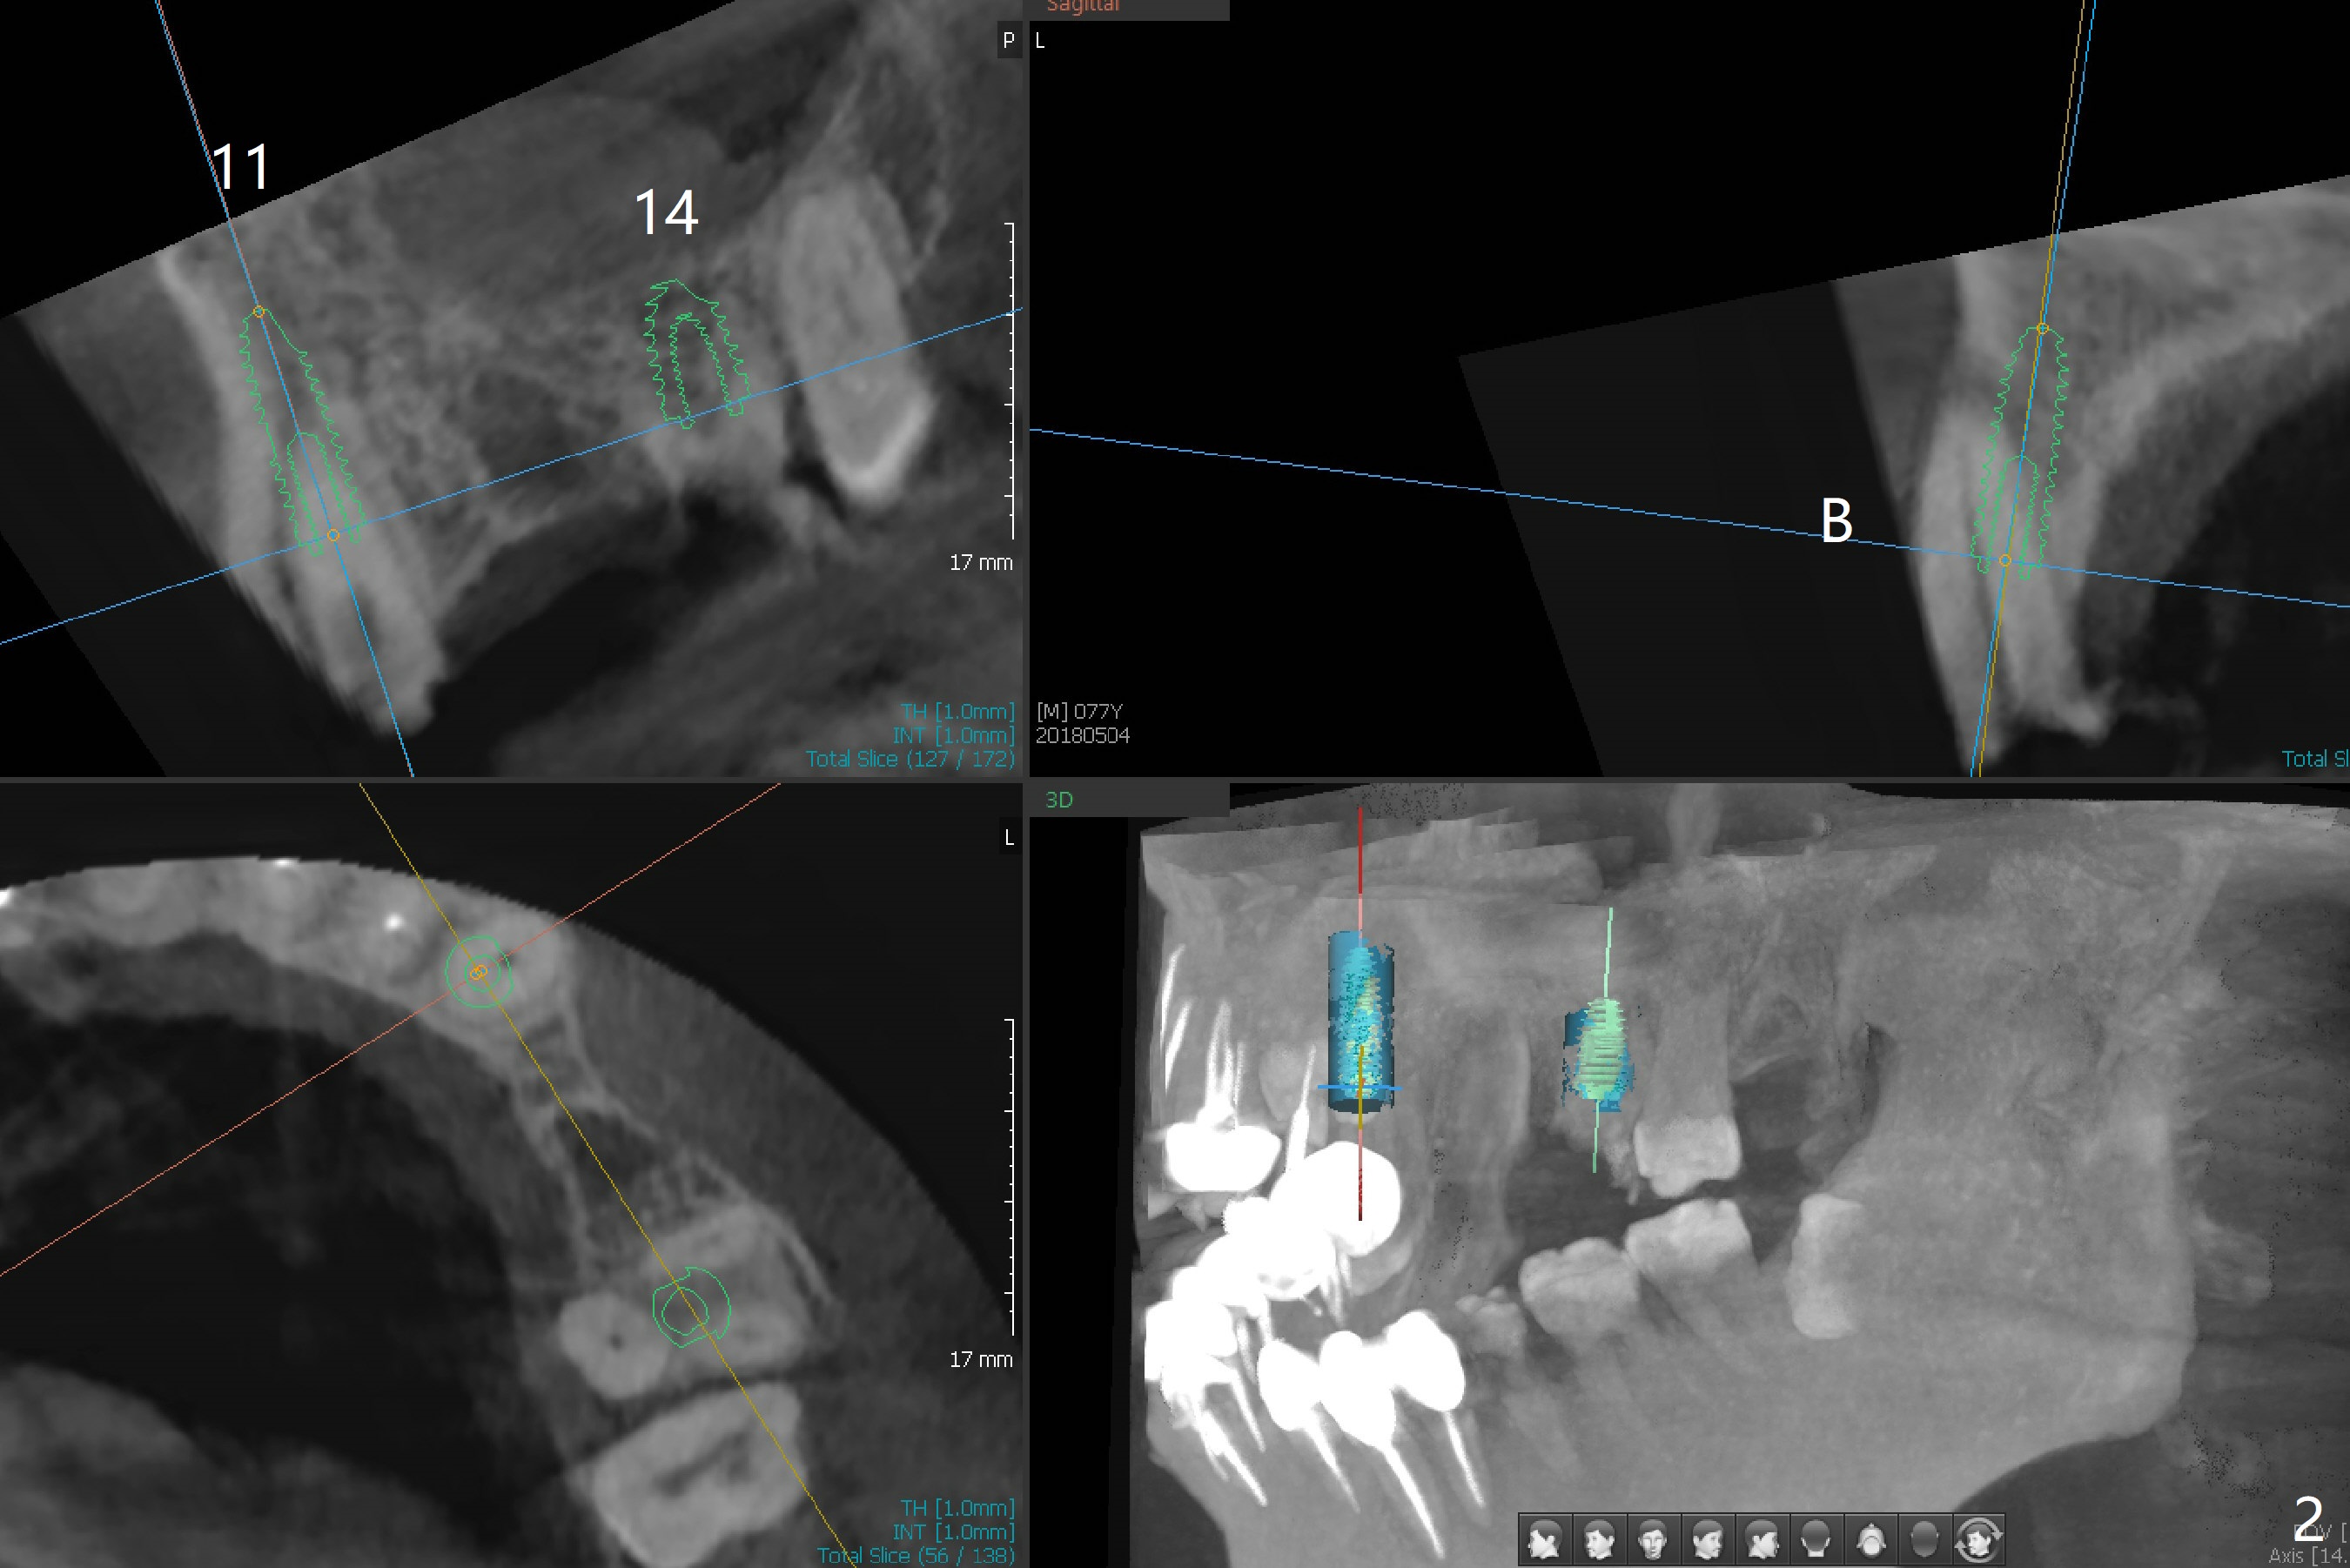

A 77-year-old man has multiple restoration with long roots (suggesting bruxism, Fig.1). The #11-14 FPD dislodges. Twenty days postop, he will travel to his home country and stays for 2 months. Four months postop, he will leave again. To strengthen provisional FPD stability and early final restoration, each implant will be placed at each edentulous area. The longest bone-level implant will be placed at #11 with bone height >20 mm (Fig.2). Since the bone width (buccopalatal) is 4 mm at #12, a 2x14(2) mm 1-piece implant is to be inserted (Fig.3); while a 3.8x10 mm 2-piece one at #13 with underprep because of low density. As the septal bone height is limited at #14 (Fig.4), a 5x8.5 mm implant is going to be placed.